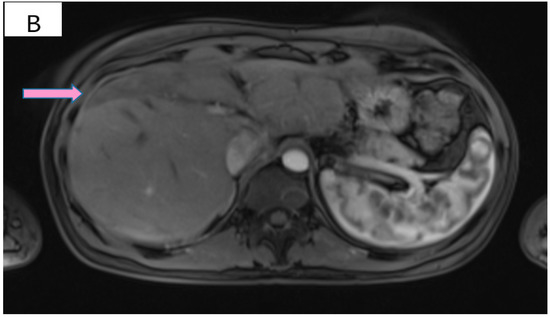

However, 2 years after the initial diagnosis, in February 2021, during the clinical and biological evaluation for an expander replacement, lab reports highlighted abnormal values of the liver enzymes—aspartate aminotransferase (AST) 155 UI/L and alanine aminotransferase (ALT) 114 UI/L. After excluding an infectious or toxic etiology, an abdominal ultrasound revealed the presence of hepatic metastases in the eighth hepatic segment. An abdominal MRI was immediately requested which showed a liver tumor mass of approximately 9.6/6.6 cm with the aspect of liver metastasis (Figure 3A). Subsequently, chest CT revealed carcinomatous lymphangitis (Figure 4A) and millimeter areas of osteolysis in the T1 and L1 vertebral bodies and the sternal body, without brain metastases on cerebral CT. During workup period, the patient’s clinical status worsened by developing symptoms of respiratory failure with dyspnoea at minimal exertion with oxygen saturation (SaO2) of 75% and rapid progressive dry cough. Furthermore, the liver was palpable 6 cm below the costal rim. Hepatic assays were exacerbated by a severe increase in AST 635 UI/L and ALT 309 UI/L (Figure 5), but with normal value of total bilirubin 1.14 mg/dL, alkaline phosphatase 179 U/L and gamma-glutamyl transferase 154 U/L with slightly increased values, albumin 3.01 g/dL, International Normalized Ratio (INR) 1.2. Tumor marker CA 15-3 was also increased (286 U/mL). At that time, the prognosis was extremely reserved.

Figure 3.

(A) Pretreatment MRI scan of the abdomen showing a large hypodense mass in the left lobe of the liver—segments VIII and IV (marked by arrows). (B) MRI scan showing a dramatic decrease in size of the metastasis (marked by arrows) in the left lobe of the liver after treatment with six cycles of Pertuzumab, Trastuzumab and Paclitaxel.

After six cycles of treatment, an imaging reassessment revealed the partial remission of liver metastases (Figure 3B), HFN with unchanged appearance, and the favorable evolution of carcinomatous lymphangitis lesions (Figure 4B) and bone metastases. In the absence of neurological symptoms, cranial imaging reassessment was not repeated. Laboratory results were within normal limits, and the CA 15-3 decreased to 33.8 U/mL. During this time, the patient changed her lifestyle, she increased her consumption of fresh fruits and vegetables and fiber and reduced her intake of processed meat, dairy and sugar. Moreover, the increase in physical activity led to gradual weight loss, about 9 kg. This time during treatment, she developed an acneiform rash and onychodystrophy, as well as grade I neutropenia and thrombocytopenia. As a result of the good therapeutic response, Paclitaxel was discontinued and hormone therapy with Fulvestrant was added to dual anti-HER2 monoclonal blockade.